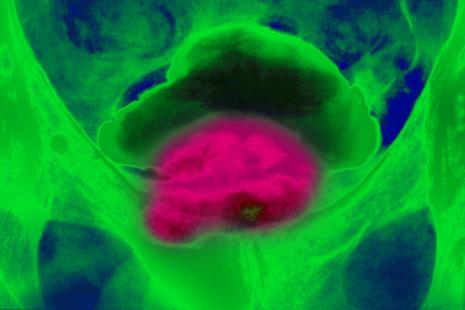

Les chercheurs du laboratoire Canther (Institut OncoLille) et de l’université libre de Bruxelles ont publié de nouvelles données sur le rôle joué par l’enzyme FTO dans le développement des métastases dans certains cancers, notamment celui de la prostate.

Les données de milliers de patients atteints de cancer ont été analysées et ont permis de constater qu’un faible niveau de FTO est associé à la présence de tumeurs plus agressives et de métastases. En baissant artificiellement les niveaux de production de FTO dans les cellules cancéreuses, les chercheurs ont aussi vu que celles-ci se propageaient plus rapidement sous forme de métastases. Des thérapies bloquant ce mécanisme sont actuellement développées et testées dans des essais cliniques.